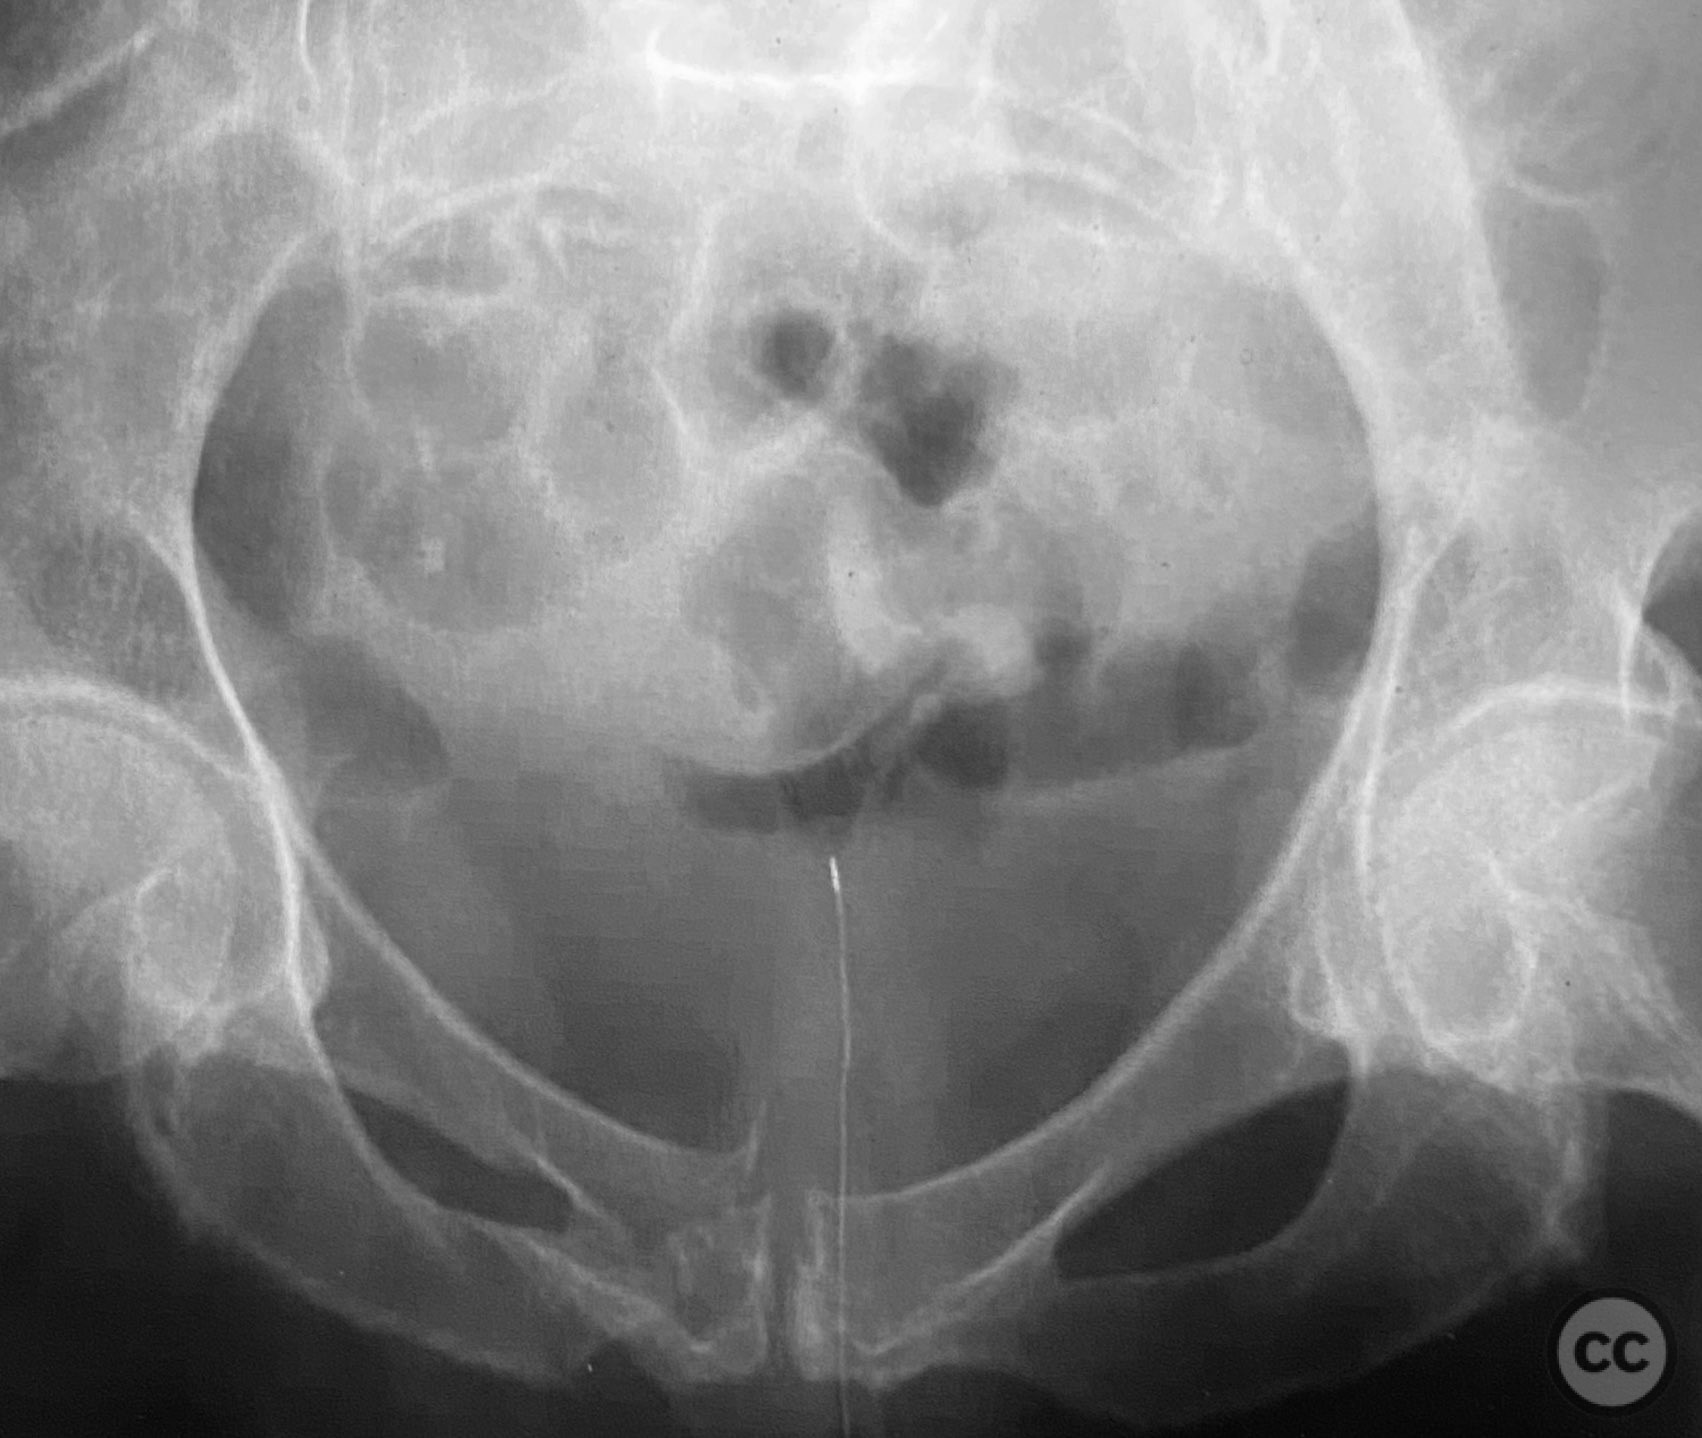

Pelvis - AO/OTA 6x